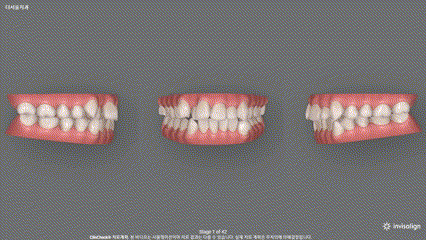

2. 클린체크 진단

저는 인비절라인으로 권유를 드렸습니다.

사실 저는 꽤 많이 사용하는 편인데요

압하도 잘 되면서 어떻게 치열이

바뀌는지 미리 알 수 있고

처음 진단 과정 그대로 치아들이 움직이는 것을

볼 수 있기 때문입니다.

어디에 힘을 주어, 이동을 시키며

누르면서 당겨야 될 지

되는지를 한 눈에 볼 수 있습니다.

또한, 몇 단계에 거쳐서 배열이 되는지

알 수 있기 때문에 환자에게 설명을 할 때에도

해당 화면을 보여드리면서

시뮬레이션을 진행을 하게 됩니다.